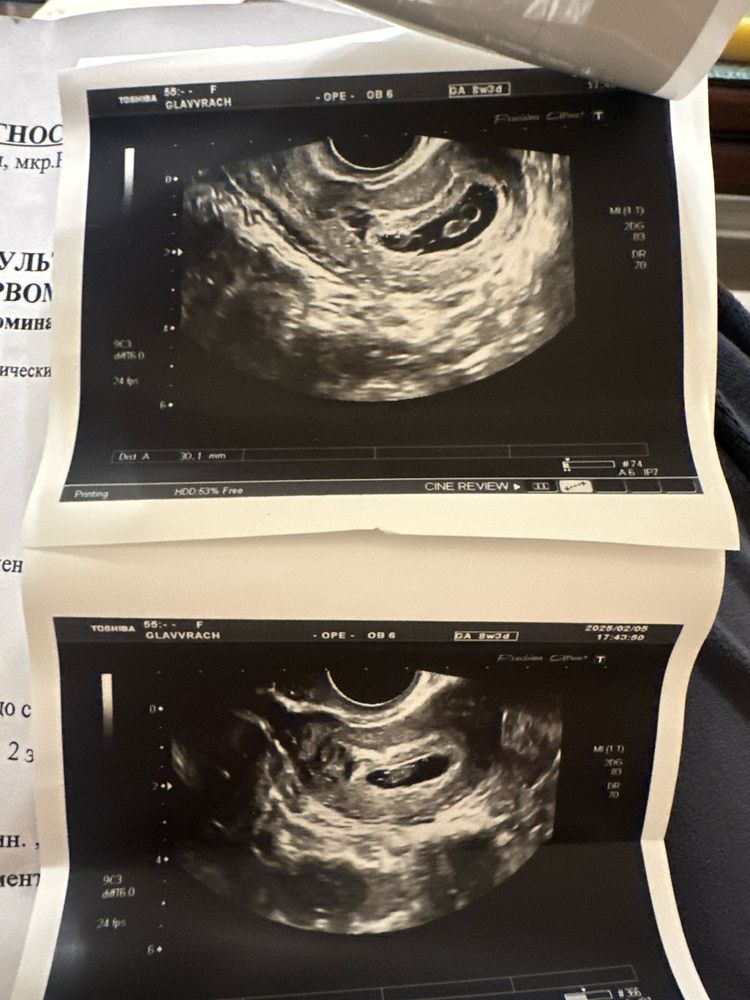

Близнецы ♥️♥️ 8 недель

Многоплодная беременностьКраткий отчет:

8 недель 3 дня

ПЯ 30 мм

1) ЖМ 3,5 мм, КТР 8 мм, СБ 156 уд/мин

2) ЖМ 3,5 мм, КТР 7,6 мм, СБ 146 уд/мин